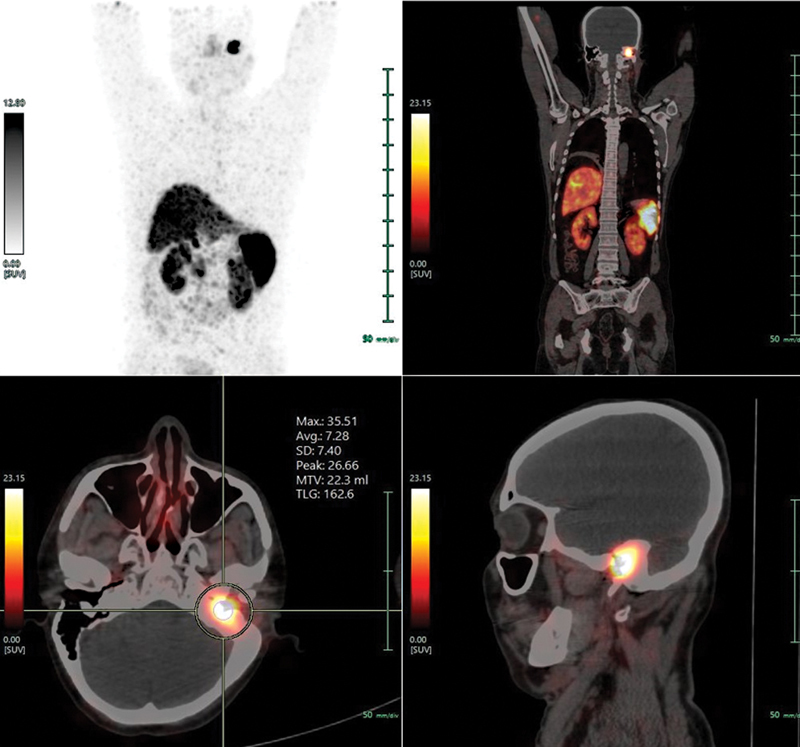

Neuroendocrine tumors of the middle ear are rare, comprising of less than 2% of primary tumors of the ear. The clinical and imaging findings of these tumors are nonspecific, and histological and immunohistochemical findings are confirmatory. Herein, we present a case of 48-year-old male, presenting with chief complaints of hearing loss of left ear with foul smelling discharge, with the initial clinical impression of otomastoiditis of the middle ear with cholesteatoma and being operated for the same, the final histopathology report inferred it as well-differentiated neuroendocrine tumor grade 1 with Ki-67 index less than 2%. Immunohistochemical examinations demonstrated positive staining of the tumor cells for cytokeratin, synaptophysin and chromogranin A, and negative for smooth muscle actin, desmin, S-100. The biochemical investigations showed raised serum chromogranin A levels. Based upon the findings on anatomical imaging modalities including high-resolution computed tomography temporal bone and magnetic resonance imaging paranasal sinuses (MRI PNS), the lesion was inferred inoperable due to involvement of dura of petrous apex, and therefore he was referred for consideration of peptide receptor radionuclide therapy (PRRT). MRI PNS also showed involvement of the horizontal part of facial nerve, indicating local aggressiveness of the tumor. 68 Ga-DOTATATE-PET/CT showed high-grade somatostatin receptor expressing soft tissue lesion involving middle ear and external auditory canal (Krenning's score 4), with low-grade metabolic activity on 18 F-FDG-PET/CT. The post-therapy scan following 177 Lu-DOTATATE PRRT, showed abnormal tracer concentration at the described site. Due to extreme rarity of this disease entity, it is important to accrue data for accurate diagnosis, proper management, and follow-up.